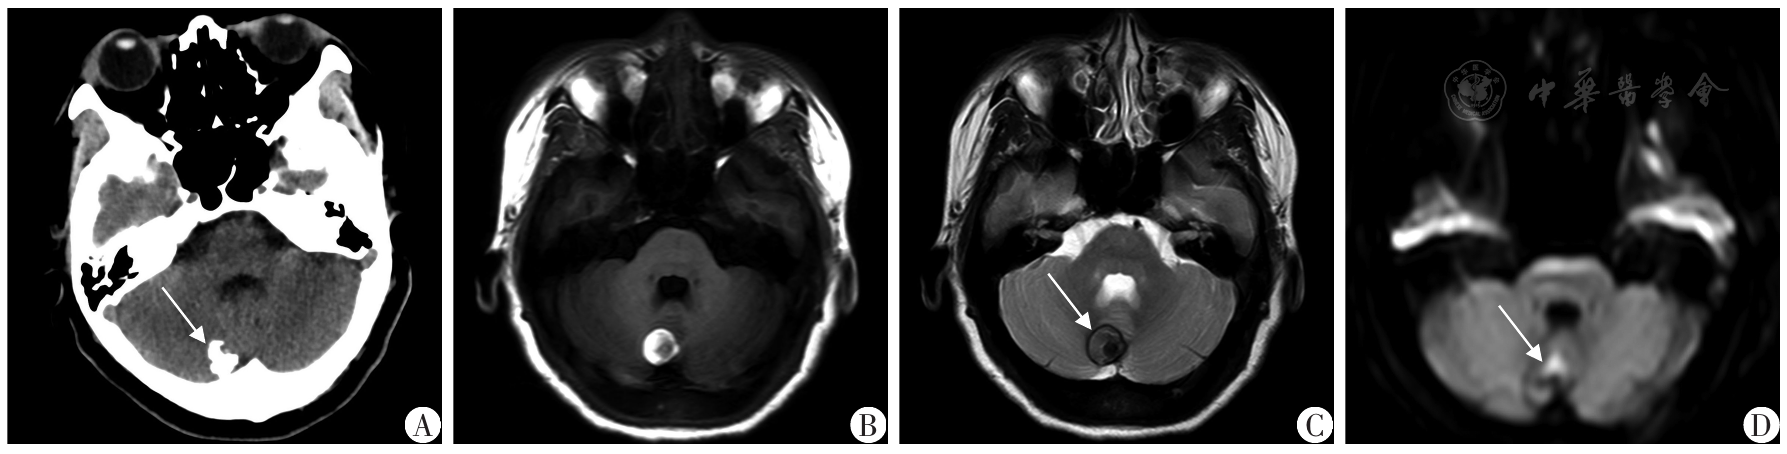

图3 右侧小脑白色表皮样囊肿患者术前影像资料A:CT以钙化密度为主(箭头所示)伴少许等密度;B:MRI T1WI呈高信号为主,中心少许稍低信号;C:MRI T2WI呈稍低信号为主,内部少许低信号,边缘见环形短T2信号含铁血黄素沉积(箭头所示);D:DWI呈部分高信号,但无弥散受限(箭头所示)

Fig.3 Preoperative imaging data of the patient with white epidermoid cyst in the right cerebellum